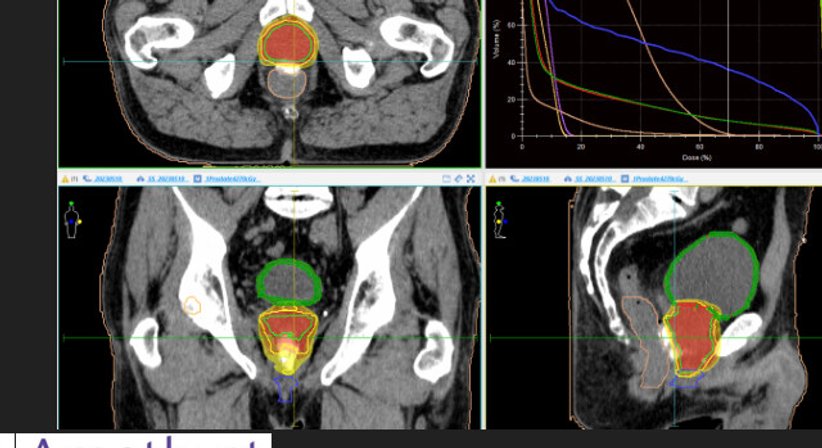

Die volumetrisch modulierte Lichtbogentherapie (VMAT) ist eine der fortschrittlichsten Techniken der externen Strahlentherapie. Dabei kommt eine Linearbeschleunigermaschine zum Einsatz, die sich im Liegen um den Patienten dreht. Das Gerät gibt Strahlungsdosen präzise an die Tumorstelle ab und begrenzt gleichzeitig die Strahlungsmenge, die das umliegende gesunde Gewebe erhält.